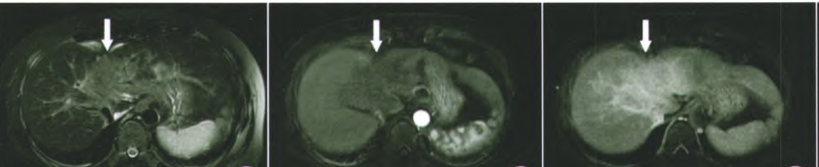

肝融合性纤维化,肝局部体积缩小,肝包膜凹陷,病灶呈 T2-FS 中等高信号,信号均匀,增强后动脉期强化不明显,延迟期呈均匀强化,相对肝实质呈高信号,内见正常走形血管影。